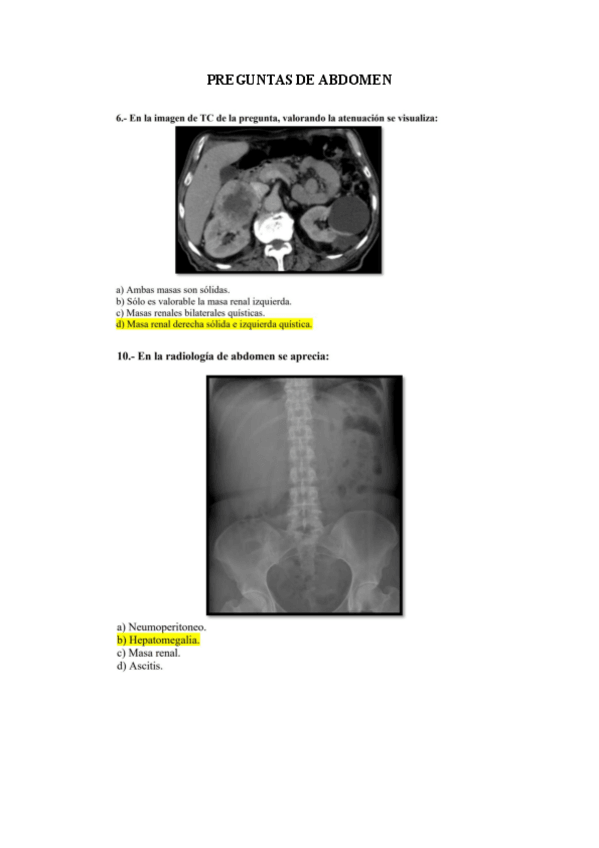

preguntas radio por bloques

He publicado nuevos examenes de 2º Radiologia General: preguntas radio por bloques

preguntas-de-abdomen.pdf